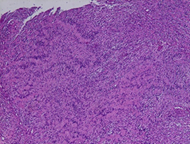

The histological examination reveals a spindle-shaped tumor

proliferation arranged in bundles. It consists of spindle cells without visible

cytoplasmic boundaries, arranged in short or intertwined bundles, with nuclear

palisades and cellular whorls. The cells have elongated nuclei, which are

non-atypical. The blood vessels have thin walls. Immunohistochemical analysis

demonstrates diffuse expression of pS100 in tumor cells. They did not express

CD34, EMA, or AML. (Figure 4)

Definitive diagnostic of schwannoma was favored. After a one-year follow-up,

Figure 4: Histological aspect